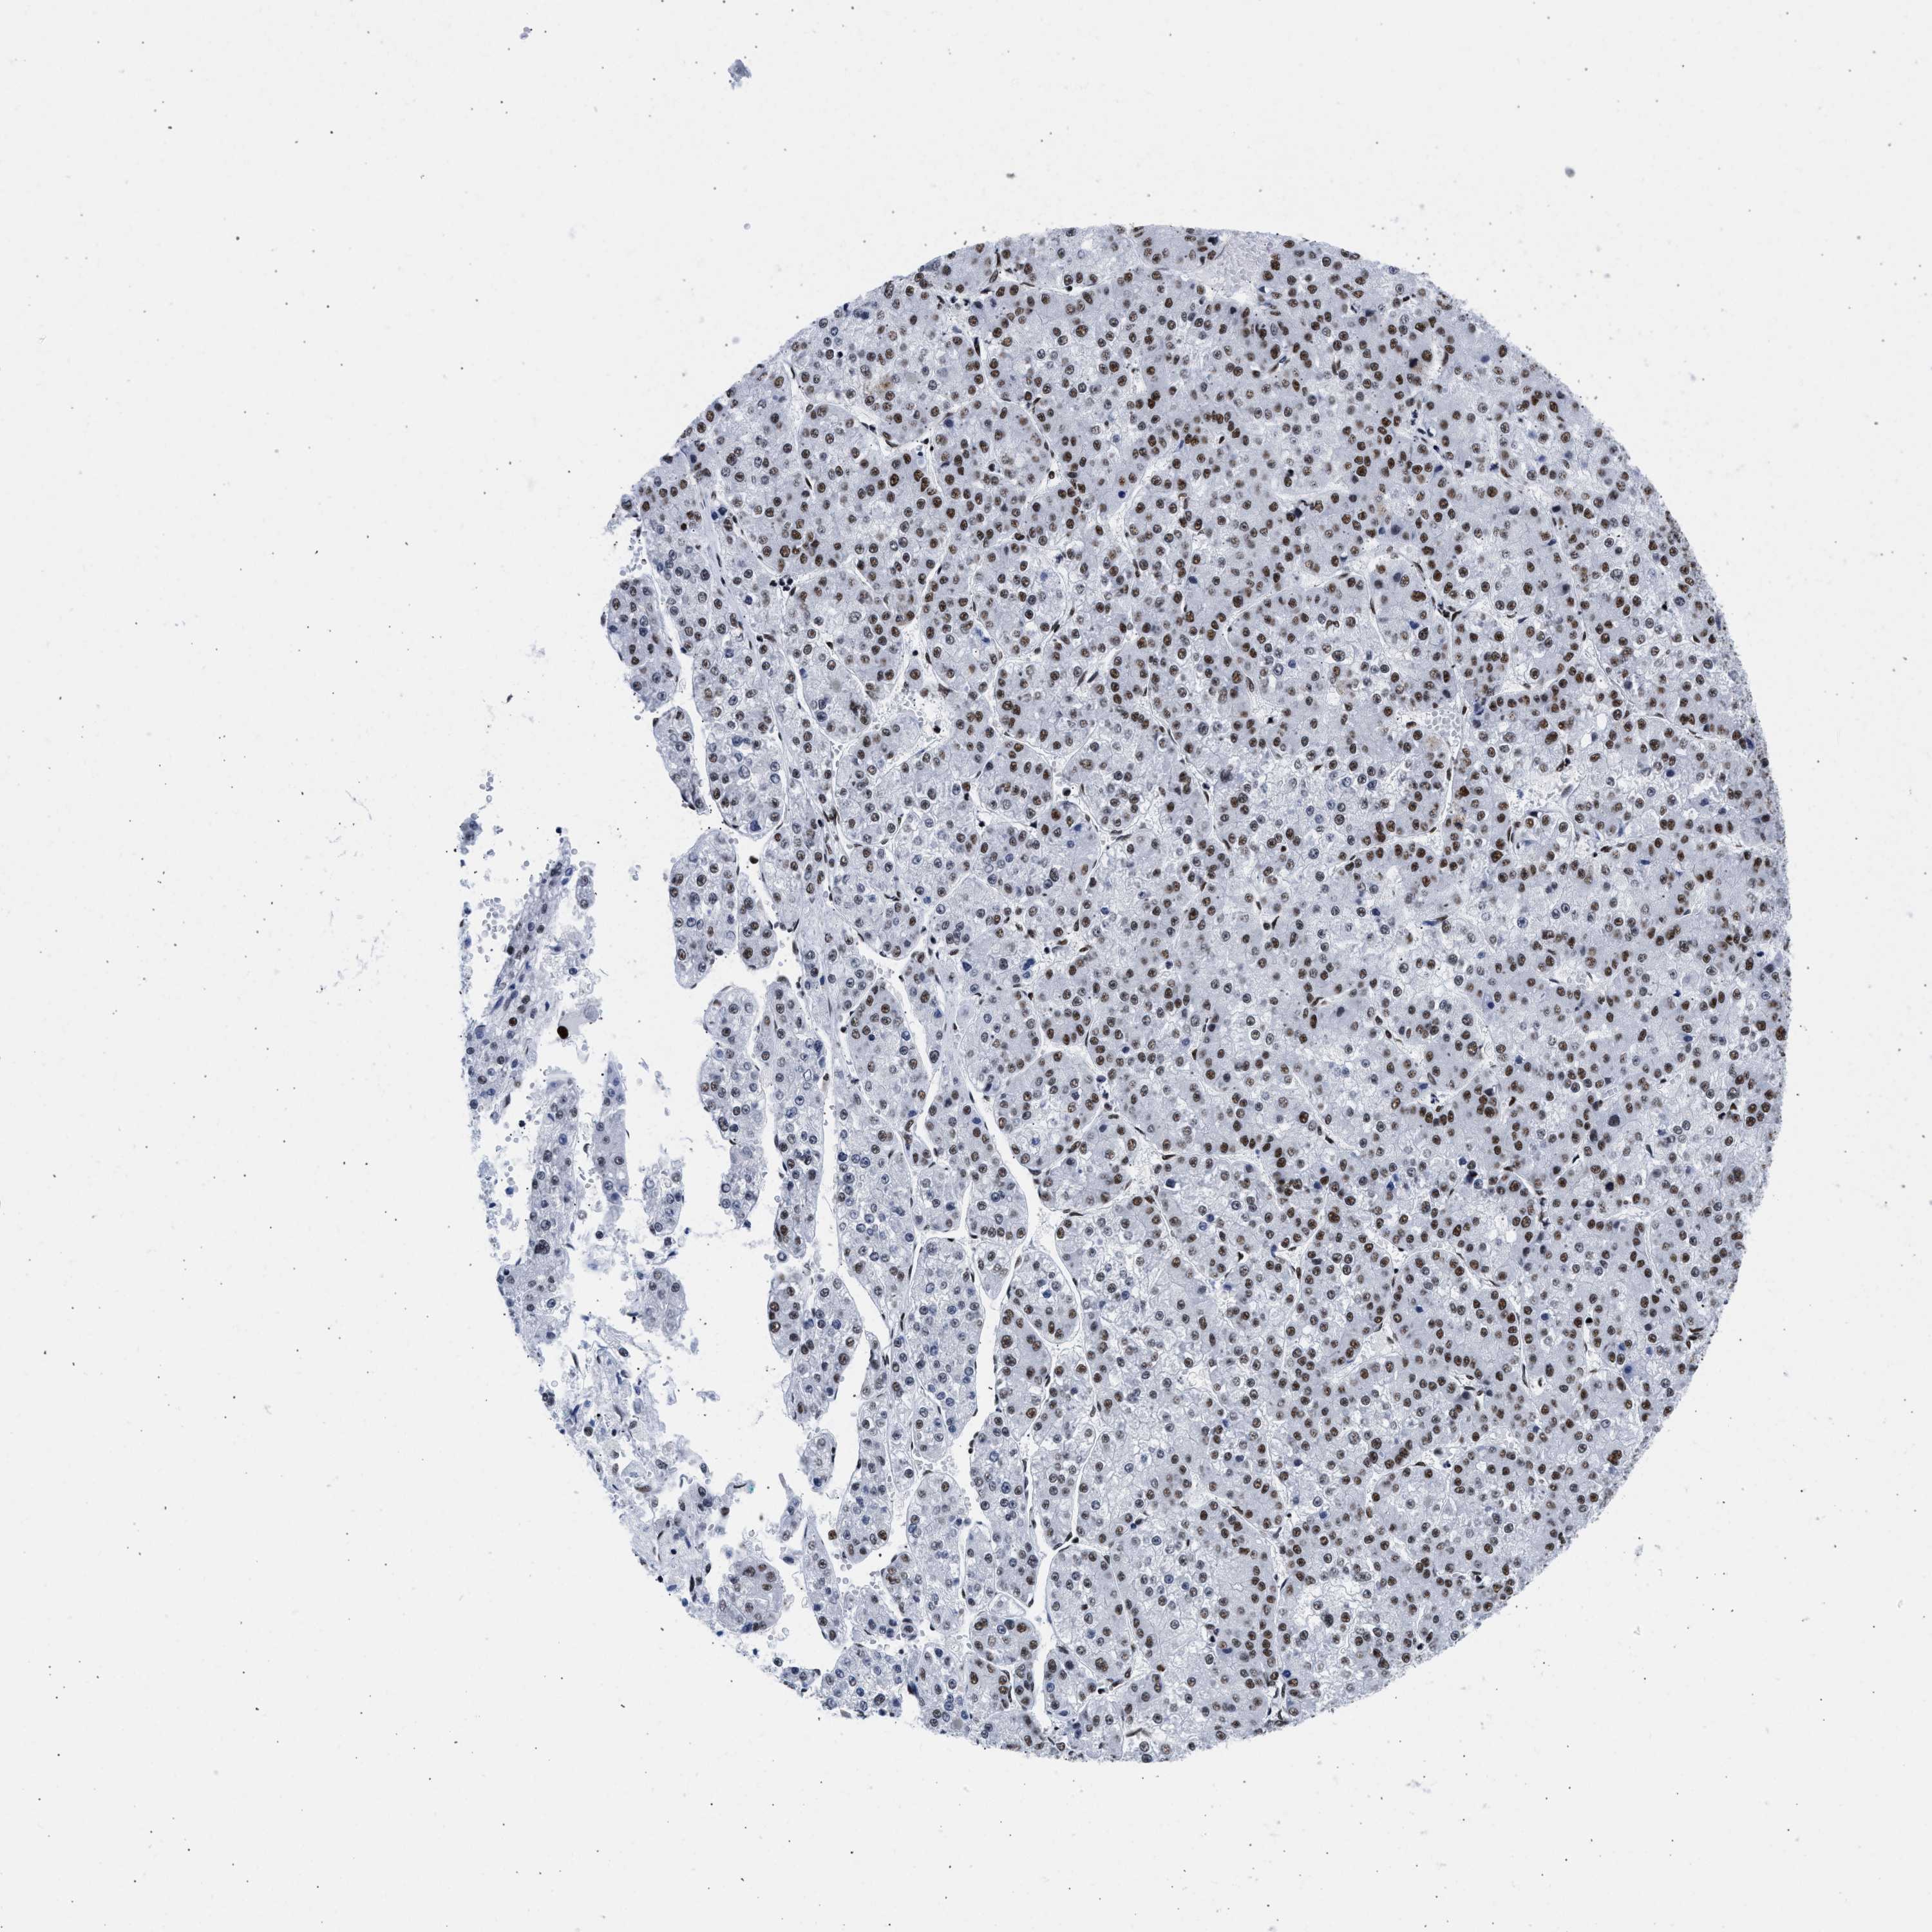

LIVER CANCER - Protein expressioni

A mouse-over function shows sample information and annotation data. Click on an image to view it in a full screen mode. Samples can be filtered based on level of antibody staining by selecting one or several of the following categories: high, medium, low and not detected. The assay and annotation is described here.

Note that samples used for immunohistochemistry by the Human Protein Atlas do not correspond to samples in the TCGA dataset.

Antibody stainingi

Antibody staining in the annotated cell types in the current human tissue is reported as not detected, low, medium, or high, based on conventional immunohistochemistry profiling in selected tissues. This score is based on the combination of the staining intensity and fraction of stained cells.

Each image is clickable and will lead to virtual microscopy that enables deeper exploration of all samples and also displays staining intensity scores, fraction scores and subcellular localization as well as patient and tissue information for each sample.

Antibody HPA018403

Staining

High

Medium

Low

Not detected

Intensity

Strong

Moderate

Weak

Negative

Quantity

>75%

75%-25%

<25%

None

Location

Nuclear

Cytoplasmic/membranous

Cytoplasmic/membranous,nuclear

Cholangiocarcinoma

Carcinoma, Hepatocellular, NOS